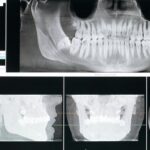

Se non si riesce a riconoscere in tempo, può sviluppare le cosiddette tasche parodontali e portare alla distruzione del legamento parodontale e dell’osso alveolare dove si trova il dente. In uno stadio più avanzato, invece, i denti perdono la loro stabilità in prossimità della gengiva, cominciano a muoversi in modo anomalo.

Questo compromette la masticazione e in alcuni casi può portare alla caduta del dente stesso.